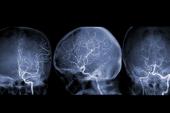

Treating Carotid Disease

The long-awaited results of the CREST-2 trials pitting carotid stenting and carotid endarterectomy individually against medical therapy alone in patients with asymptomatic carotid stenosis also came out this year. Stenting, but not surgery, demonstrated superiority to medical therapy when it came to a composite of any stroke or death within the first 44 days, or ipsilateral ischemic stroke within 4 years of follow-up.

“The interesting part for carotid intervention right now is that there seems to be a clear divide that’s happened between asymptomatic and symptomatic [patients],” Secemsky said, noting that those with stroke or TIA are primarily going to stroke centers and being managed by neurologists, neurointerventionalists, and neurosurgeons. Asymptomatic patients, on the other hand, tend to be managed by multidisciplinary teams of cardiologists, vascular surgeons, and interventional radiologists.

CREST-2 “is going to shake up this space a little bit” and suggests that for patients with a reasonable life expectancy, “probably early intervention on asymptomatic carotid disease is the right decision,” he said. “We were still questioning that before CREST-2, so that definitely has some legs and I think it will be really interesting to see how it plays out in clinical practice.”